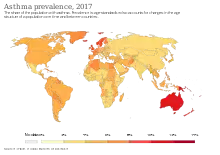

Selon l'OMS, en 2016, près de 334 millions de personnes souffrent d'asthme dans le monde. Ce nombre, en constante augmentation, est souvent sous-estimé à cause de mauvais diagnostics[15].

Expansion récente de l’asthme

On note une expansion rapide de la maladie depuis les années 1960 dans les pays développés[19],[6]. Il est surtout présent dans les pays connaissant une forte industrialisation ou une industrialisation en développement rapide. Il est par exemple peu connu en Afrique subsaharienne. En 1999, des chercheurs de l'International Study of Asthma and Allergies in Childhood ont quantifié quelques données concernant l'asthme, en mesurant le pourcentage d'asthme et d'allergies parmi les 13-14 ans dans différents pays :

- Suède et Finlande : entre 10 % et 20 % ;

- Albanie, Roumanie, Russie, Géorgie et Ouzbékistan : <6 % ;

- Royaume-Uni : >30 %.